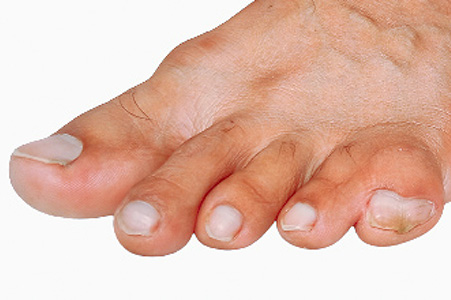

How Psoriatic Arthritis Affects the Feet

Psoriatic arthritis is a long-term inflammatory condition that can affect the joints, skin, and nails of the feet. Many people experience swelling and pain in the toes, sometimes causing an entire toe to appear enlarged or sausage-shaped. This symptom indicates widespread inflammation within a toe joint and surrounding tissues. Stiffness in the feet and ankles may be worse in the morning or after periods of rest, making walking uncomfortable. Some people develop flattening of the arches or changes in toe position. This can increase pressure on certain areas and lead to corns or calluses. Heel pain may also occur when the inflammation affects the tissue that supports the arch. Nail changes, such as thickening, crumbling, or small dents, also can be early signs. A podiatrist can assess joint swelling, foot structure, and skin or nail problems, and may use imaging tests or recommend supportive footwear or custom orthotics. If you have symptoms of psoriatic arthritis, it is suggested that you make an appointment with a podiatrist.